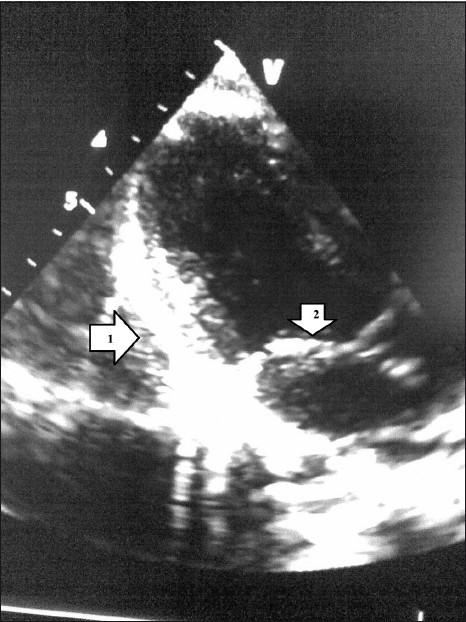

Aetiology of pericardial calcifications can be multifactorial. Tuberculosis has been reported as the most common cause. Other known causes include uraemia, asbestosis, post-traumatic or postoperative. We report a rare case of pericardial calcification seen in a patient with established acute intermittent porphyria. A direct causal relationship cannot be established between porphyria and pericardial calcification, but it may be due to deposition of the porphyrin in the pericardium.

心包钙化的病因可能是多因素的。据报道,结核病是最常见的病因。其他已知病因包括尿毒症、石棉沉着病、创伤后或术后。我们报告了一例在确诊为急性间歇性卟啉病的患者中出现的心包钙化罕见病例。卟啉病与心包钙化之间无法确立直接的因果关系,但可能是由于卟啉在心包中的沉积所致。